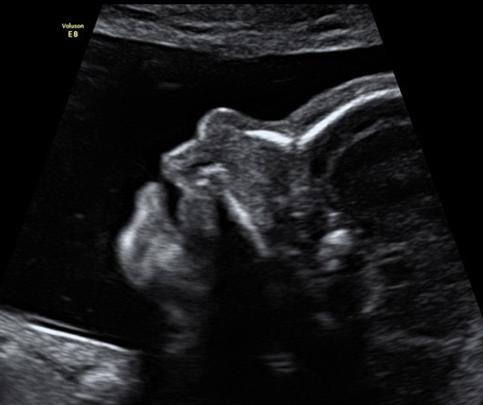

经常可以看到一些宝妈拿着B超报告跑过来,医生我的宝宝B超做出来没有鼻骨怎么办,以后会不会是个塌鼻子呀,会不会很难看,是不是可以隆鼻,如果要隆鼻的话几岁最好,诸如此类的话语。

其实B超提示鼻骨缺如,远没有宝妈们想的那么简单,胎儿鼻骨缺如是一种超声软指标,出来这个词或许宝妈们会有点别扭,但是我这么一讲或许你就了解了,临床上医生会归纳一些超声指标来与胎儿染色体异常联系起来,也就是将当出现某种超声软指标时,提示某种胎儿染色体异常概率增加。研究提示21-三体胎儿中鼻骨缺失发生率比较高(60-80%),而且在18三体,13三体中胎儿鼻骨缺失也较高,统计学显示21-三体鼻骨缺失为普通人的6一10倍,故当出现鼻骨缺如时,宝妈们一定要排除21-三体。

但是宝妈也不用特别紧张,不要以为胎儿鼻骨缺如就被判了死刑,其实在正常染色体人群中,胎儿鼻骨缺失和鼻骨发育不良的发生概率在1%-3%,看似很低,其实不然正常人群基数大,因此,胎儿鼻骨缺失和鼻骨发育不良的人数是不少的。也就是讲鼻骨缺如的胎儿大部分还是染色体正常的,只是单纯的鼻骨缺失或发育不良而已。

但是当出现孤立性的胎儿鼻骨缺如时,宝妈们也不能掉以轻心,需要排除胎儿染色体异常,尤其是21-三体,才可以高枕无忧,一般建议无创DNA检查,或者羊水穿刺核型分析及微阵列排除染色体异常,虽然羊水穿刺核型分析及微阵列理应该是最合适的,但是考虑到羊水穿刺属于有创操作,存在一定几率妊娠丢失的可能,宝妈们可以选择无创DNA检查进行检查,毕竟无创DNA检查对21-三体,18-三体,13-三体的检出率较高,尤其是21-三体检出率高达99%。如果无创DNA检查提示低风险,那么问题就不大了。

问题来了,有时胎儿鼻骨缺如往往会伴随着其它超声软指标异常比如NT增厚,颈后皮褶厚度增加,肠管回声增强,肢体短小,侧脑室增宽,心室强光点,肾盂扩张等),则胎儿染色体异常的风险增加为17.65%;如果合并其他胎儿结构异常或胎儿宫内生长受限,则胎儿染色体异常的风险增加为83.33%。此时就需要羊水穿刺核型分析及微阵列,甚至有些因为孕周的原因只能选择风险较大的脐血穿刺核型分析及微阵列,此种情况不建议做无创DNA检查。

总结,胎儿鼻骨缺如的发生率大概为17-35 ‰。宝妈们碰到胎儿鼻骨缺如也不用惊慌,大部分宝宝是生理学的鼻骨缺如,但是也不要马虎,一定要记得做个无创DNA检查,或羊水穿刺核型分析及微阵列,如果排除染色体异常,那么胎儿鼻骨缺如就让他缺如好了,就是个塌鼻子而已,不影响生活质量,如果爱美,大不了花点钱以后隆个鼻,想隆多高的都行。祝好孕。